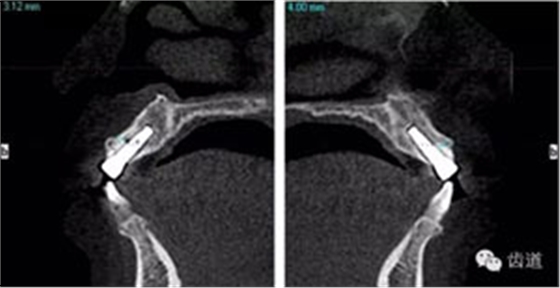

術(shù)后CT

戴牙后CT